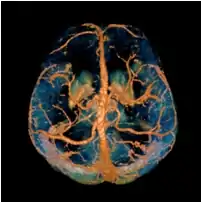

COSMOS assumes a model-free susceptibility distribution and keeps full fidelity to the measured data. This method has been validated extensively in in vitro, ex vivo and phantom experiments. Quantitative susceptibility maps obtained from in vivo human brain imaging also showed high degree of agreement with previous knowledge about brain anatomy. Three orientations are generally required for COSMOS, limiting the practicality for clinical applications. However, it may serve as a reference standard when available for calibrating other techniques.